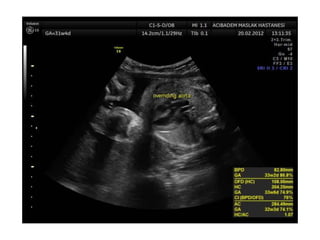

Binder Phenotype

a flat profile and depressed nasal bridge.

Short nose, short columella, flat naso-labial angle and

perialar flattening